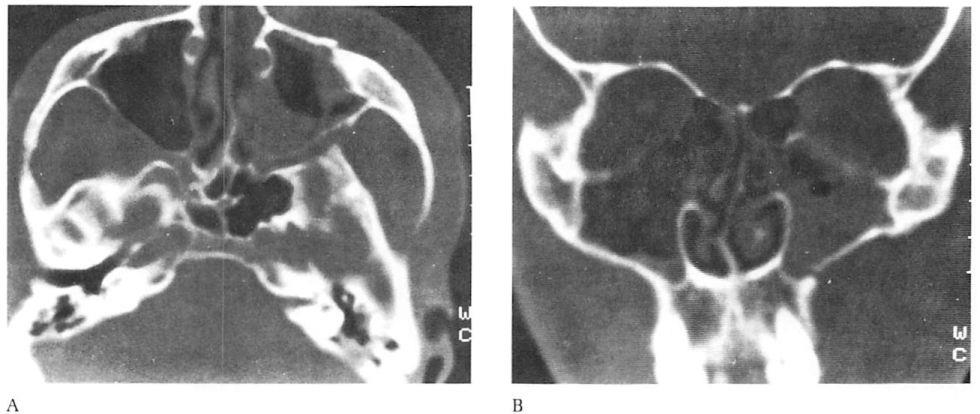

Fig 4. Highly comminuted fracture of supraorbital portion of large frontal sinus that extends to lateral orbit treated with open reduction and microplate and screw fixation. (A) Preoperative axial computed tomographic (CT) scan. (B) Postoperative axial CT shows stable reduction 2 months after injury. Note symmetrical contour of frontal soft tissues.

Fig 4. Highly comminuted fracture of supraorbital portion of large frontal sinus that extends to lateral orbit treated with open reduction and microplate and screw fixation. (A) Preoperative axial computed tomographic (CT) scan. (B) Postoperative axial CT shows stable reduction 2 months after injury. Note symmetrical contour of frontal soft tissues.

In this series only 1 patient had clinically apparent loss of fracture reduction in the area stabilized by microplates (see Fig 4). Of the 42 patients, 23 had CT scans in the early postoperative period and, with the exception of the patient presented in Figure 4, revealed near anatomical reduction of their fractures. There were 2 patients who required secondary surgery to improve globe position as a result of inadequate initial internal orbit reconstruction.

The patient presented in Figure 4 also had an open wound with extensive soft tissue injuries that were sutured in the emergency room. The patient developed extensive necrosis of the tem-poralis requiring debridement and intravenous antibiotic therapy. Six weeks later this patient presented with orbital cellulitis. Debridement at this time revealed further muscle necrosis and loose microfixation hardware, which was removed and replaced with miniplates after appropriate debridement. A secondary reconstruction was performed 6 months after the initial surgery without incident.